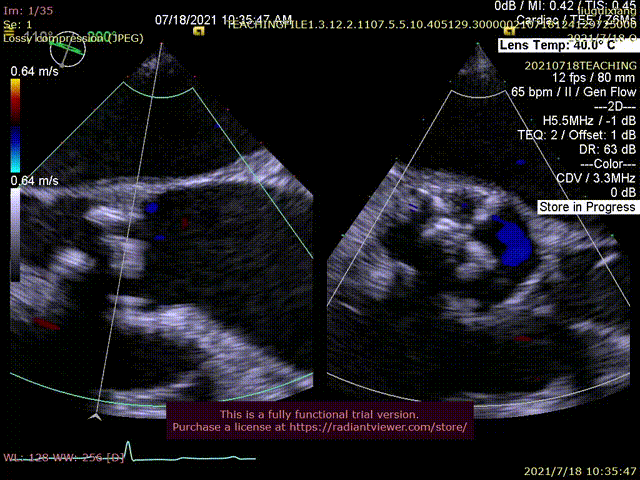

患者为79岁老年女性,一周前出现无诱因胸闷不适,咳喘明显,由当地医院转至鼓楼医院急诊。超声心动图显示左房内径增大,左室心肌增厚,EF值50%,主动脉瓣峰值流速5.68m/s,峰值压差128mmHg,主动脉瓣瓣膜增厚、粘连、钙化,提示主动脉瓣重度狭窄伴轻度关闭不全。二尖瓣中度关闭不全,三尖瓣轻-中度关闭不全伴轻度肺动脉高压,少量心包积液。

超声提示重度狭窄

术中三维超声测量距离及左冠血流